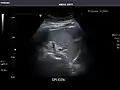

Abdominal Ultrasound (Full Exam)

STRUCTURED REPORT

(Technique: Transabdominal ultrasonography; Device: Toshiba Aplio XG)

Spleen: Normal in size.

IMPRESSION:

Normal abdominal ultrasound.

Spleen -